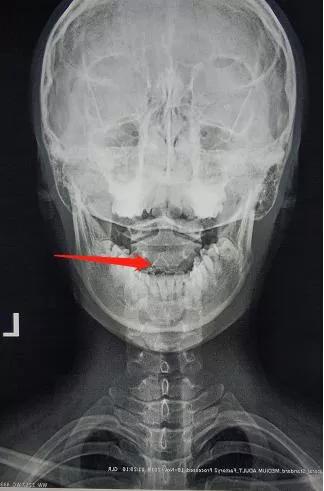

7、寰枢椎错位。(重中之重)

颈椎寰枢椎错位